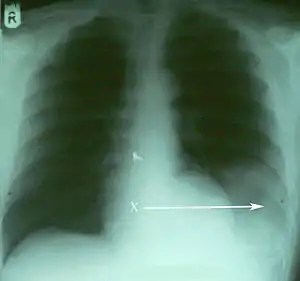

| اشعهایکس، طحال را در پایین و سمت چپ از حفره قفسه سینه نشان دادهاست.[1] | |